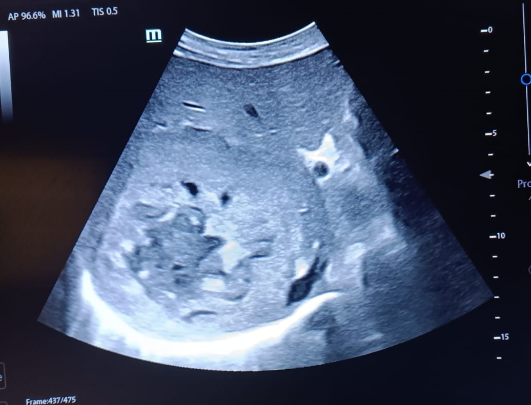

Hallazgos ecográficos

Murphy ecográfico positivo, lesión hepática única heterogénea de 4,5 x 7,5 cm aproximadamente.

La masa es predominantemente hipoecoica aunque presenta áreas heterogéneas: zonas hiperecogénicas y otras anecoicas (que podrían sugerir áreas de necrosis o cambios quísticos).